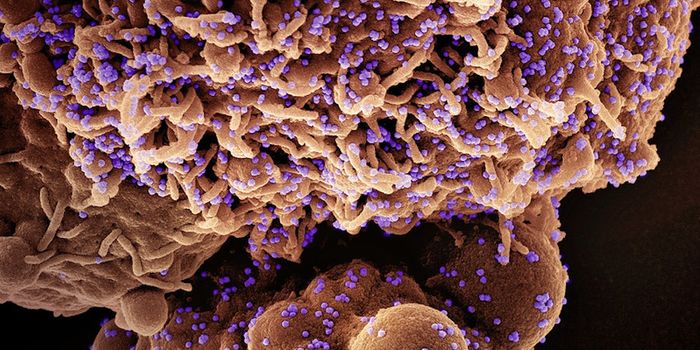

APR 07, 2023MicrobiologyScientists are still learning about SARS-CoV-2, and the illness it causes, COVID-19. While we know a lot about how the v ...